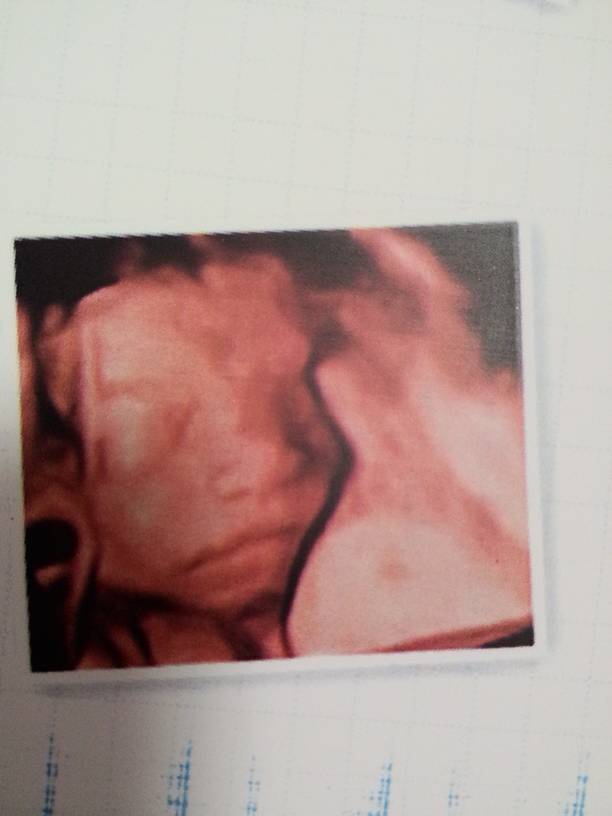

四维彩超一切正常,就是胎儿脐带绕颈一周,好担心宝宝,希望他会把脐带绕回来吧!不知道脐带绕颈会不会很危险,各位宝妈有相同的情况吗?

有脐带绕颈现象也是常见的不必担心的,在孕中期,只要胎儿继续在活动,说不定缠绕的脐带就会自行解开,最好的办法是定期做检查,听医生的建议,必要时才考虑剖宫产。